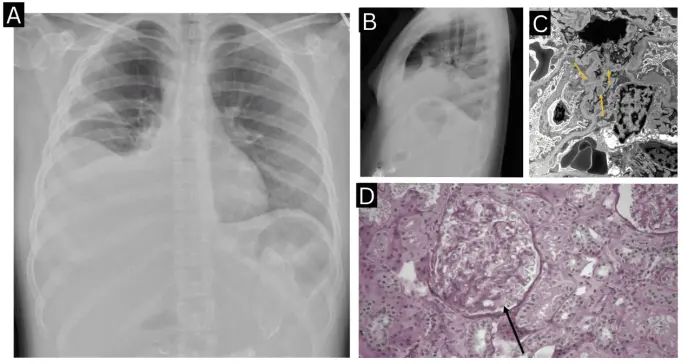

La tomografía computarizada abdomino-pélvica evidenció enterocolitis difusa severa con ascitis de gran volumen. Durante la hospitalización, la paciente desarrolló disnea y mayor distensión abdominal, requiriendo oxígeno suplementario. La radiografía de tórax mostró derrames pleurales bilaterales moderados.